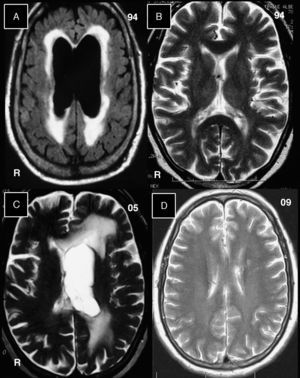

Imágenes de resonancia magnética cerebral sin la administración de gadolinio. A) Correspondiente al año 1994, en tiempo FLAIR aparece dilatación ventricular bilateral con hiperintensidades que rodean a las cavidades. B) La imagen en T2 se efectuó un mes después de la figura 1 y con la derivación ventrículo-auricular ya efectuada. Las cavidades ventriculares se normalizaron. C) Correspondiente al año 2005, en tiempo T2, muestra en el hemisferio cerebral izquierdo dilatación del ventrículo lateral, con hiperintensidades que rodean a este ventrículo. D) Correspondiente al año 2009, en tiempo T2, y no muestran alteraciones en el parénquima cerebral, y los ventrículos laterales son de tamaño normal.

Se reincorporó ST (800mg y 160mg, respectivamente, 2 veces por día) continuado y ceftriaxona intramuscular (1g 2 veces por día) durante 2 meses. Los síntomas desaparecieron y un control de resonancia cerebral a los 77 años no mostraba lesiones (fig. 1D). En un último control en 2010, permanecía asintomático y medicado con ST en iguales dosis. Esta historia clínica fue presentada en formato de afiche en el 86° Congreso Anual de la Asociación Americana de Neuropatología del 9 al 13 de junio de 2010, y publicada como resumen1. Nuestro objetivo es difundirla en idioma español.